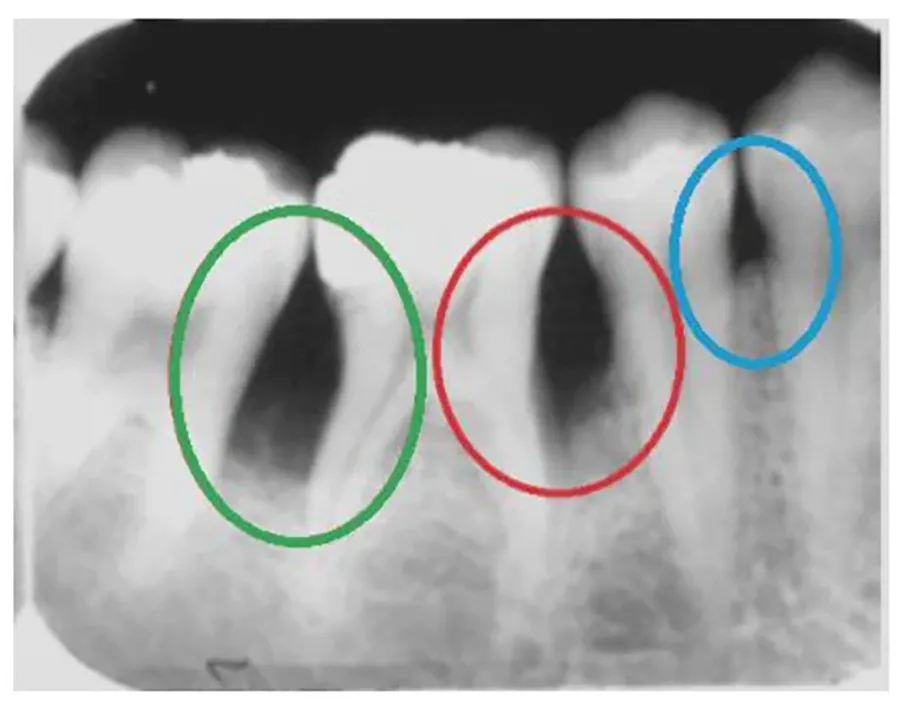

歯石は歯ブラシが届きにくい歯と歯茎の間、そして歯茎の深い部分の歯の根元に多くたまります。また、歯茎を損傷させる主な原因は、目に見える歯石ではなく、歯茎の深い部分に隠れている歯石です。

このような歯石が細菌や毒素を放出し、歯茎に炎症を引き起こし、歯槽骨を溶かす役割を果たします。炎症によって歯槽骨が溶けると、しっかり支えていた歯がぐらつき、最終的に抜けてしまうことがあります。したがって、

歯茎と歯の間の深い部分にある歯石を必ず取り除くルートプレーニングが重要になります。歯茎の疾患の自己診断方法